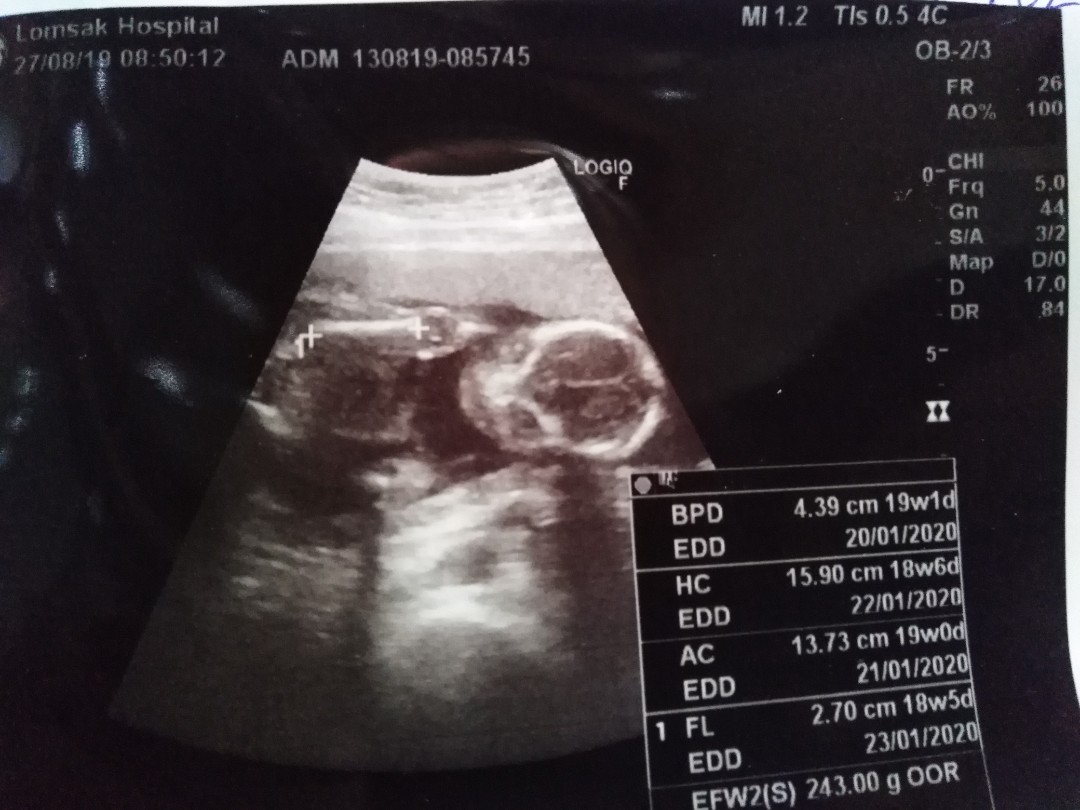

โชว์ผลซาวด์กันค่ะ

คุณลุงหมอบอกมีกลีบ?ใครมีกลีบ ใครมีแท่ง ลงมาอวดกันจร้า

หมอบอกผู้หญิง80%จ้า